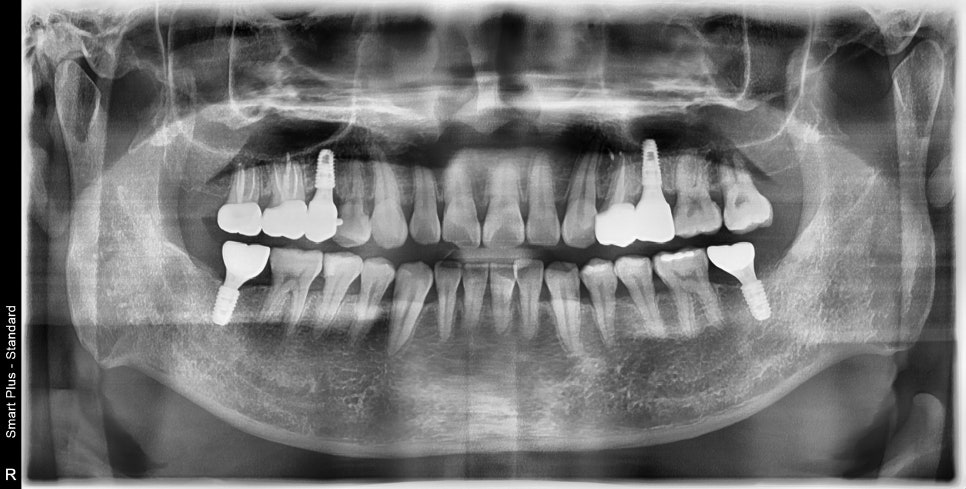

보철치료까지 완성될 때쯤은 임플란트의 고정력이 좋아질 시기와 비슷하여

비슷한 시기에 보철치료까지 완성할 수 있었습니다.

신경치료와 보철치료가 완료될 때쯤

남아있던 한 부위 임플란트를 수술할 수 있었습니다.

아직은 뼈가 무른 상태였기 때문에 이것 또한

기다리며 나머지 충치치료를 진행했습니다.

앞니 쪽의 새까맣던 충치 부위도 치아색에 맞춰서 레진 치료까지 마무리되었습니다

사진으로 요약해서 볼 때는 짧게 느껴지지만

기다리는 시간까지 하면 치료 기간은 반년 정도 걸렸습니다.